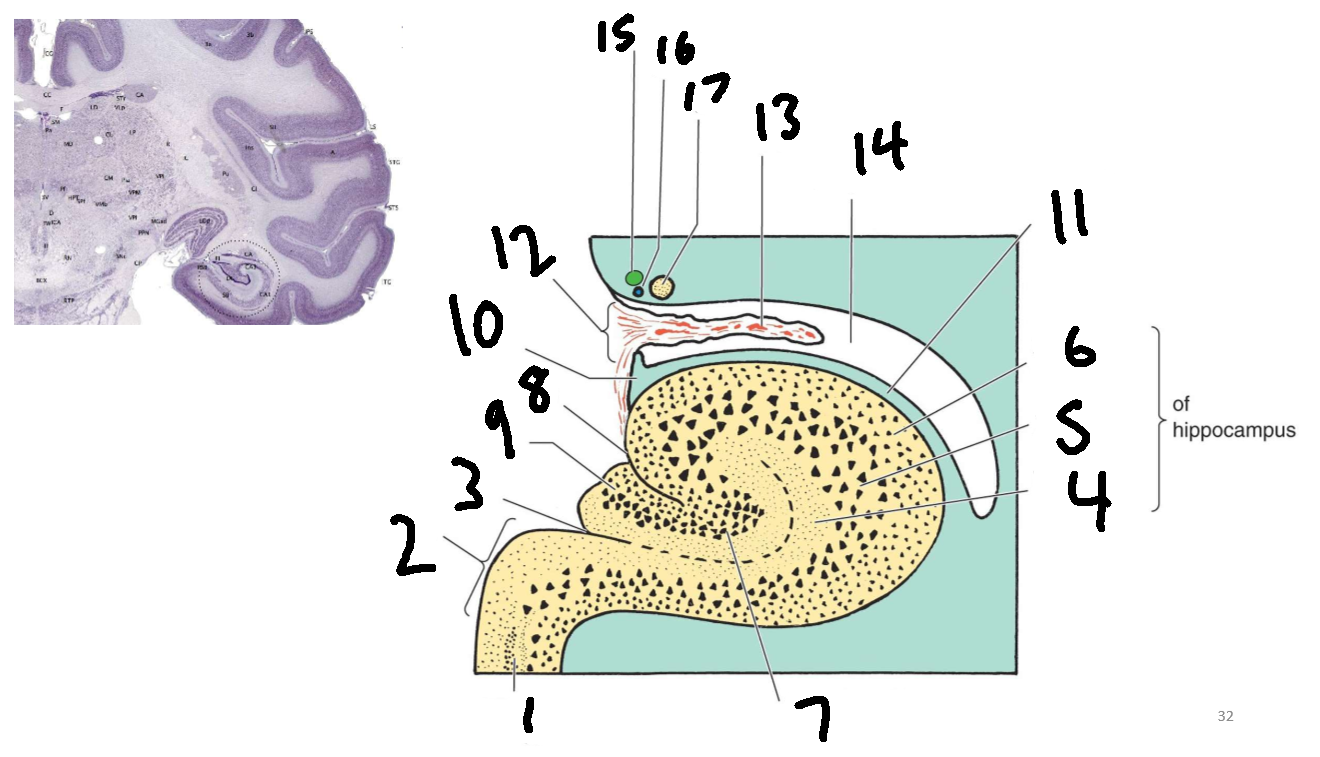

What is 1?

parahippocampal gyrus

What is 2?

subiculum

What is 3?

hippocampal sulcus

What is 4?

molecular layer

What is 5?

pyramidal layer

What is 6?

polymorphic cell layer

What is 7?

granule cell layer of dentate gyrus

What is 8?

fimbriodentate sulcus

What is 9?

dentate gyrus

What is 10?

fimbria of hippocampus

What is 11?

alveus

What is 12?

choroid fissure

What is 13?

choroid plexus

What is 14?

temporal horn of lateral ventricle

What is 15?

stria terminalis

What is 16?

thalamostriate vein

What is 17?

tail of caudate nucleus